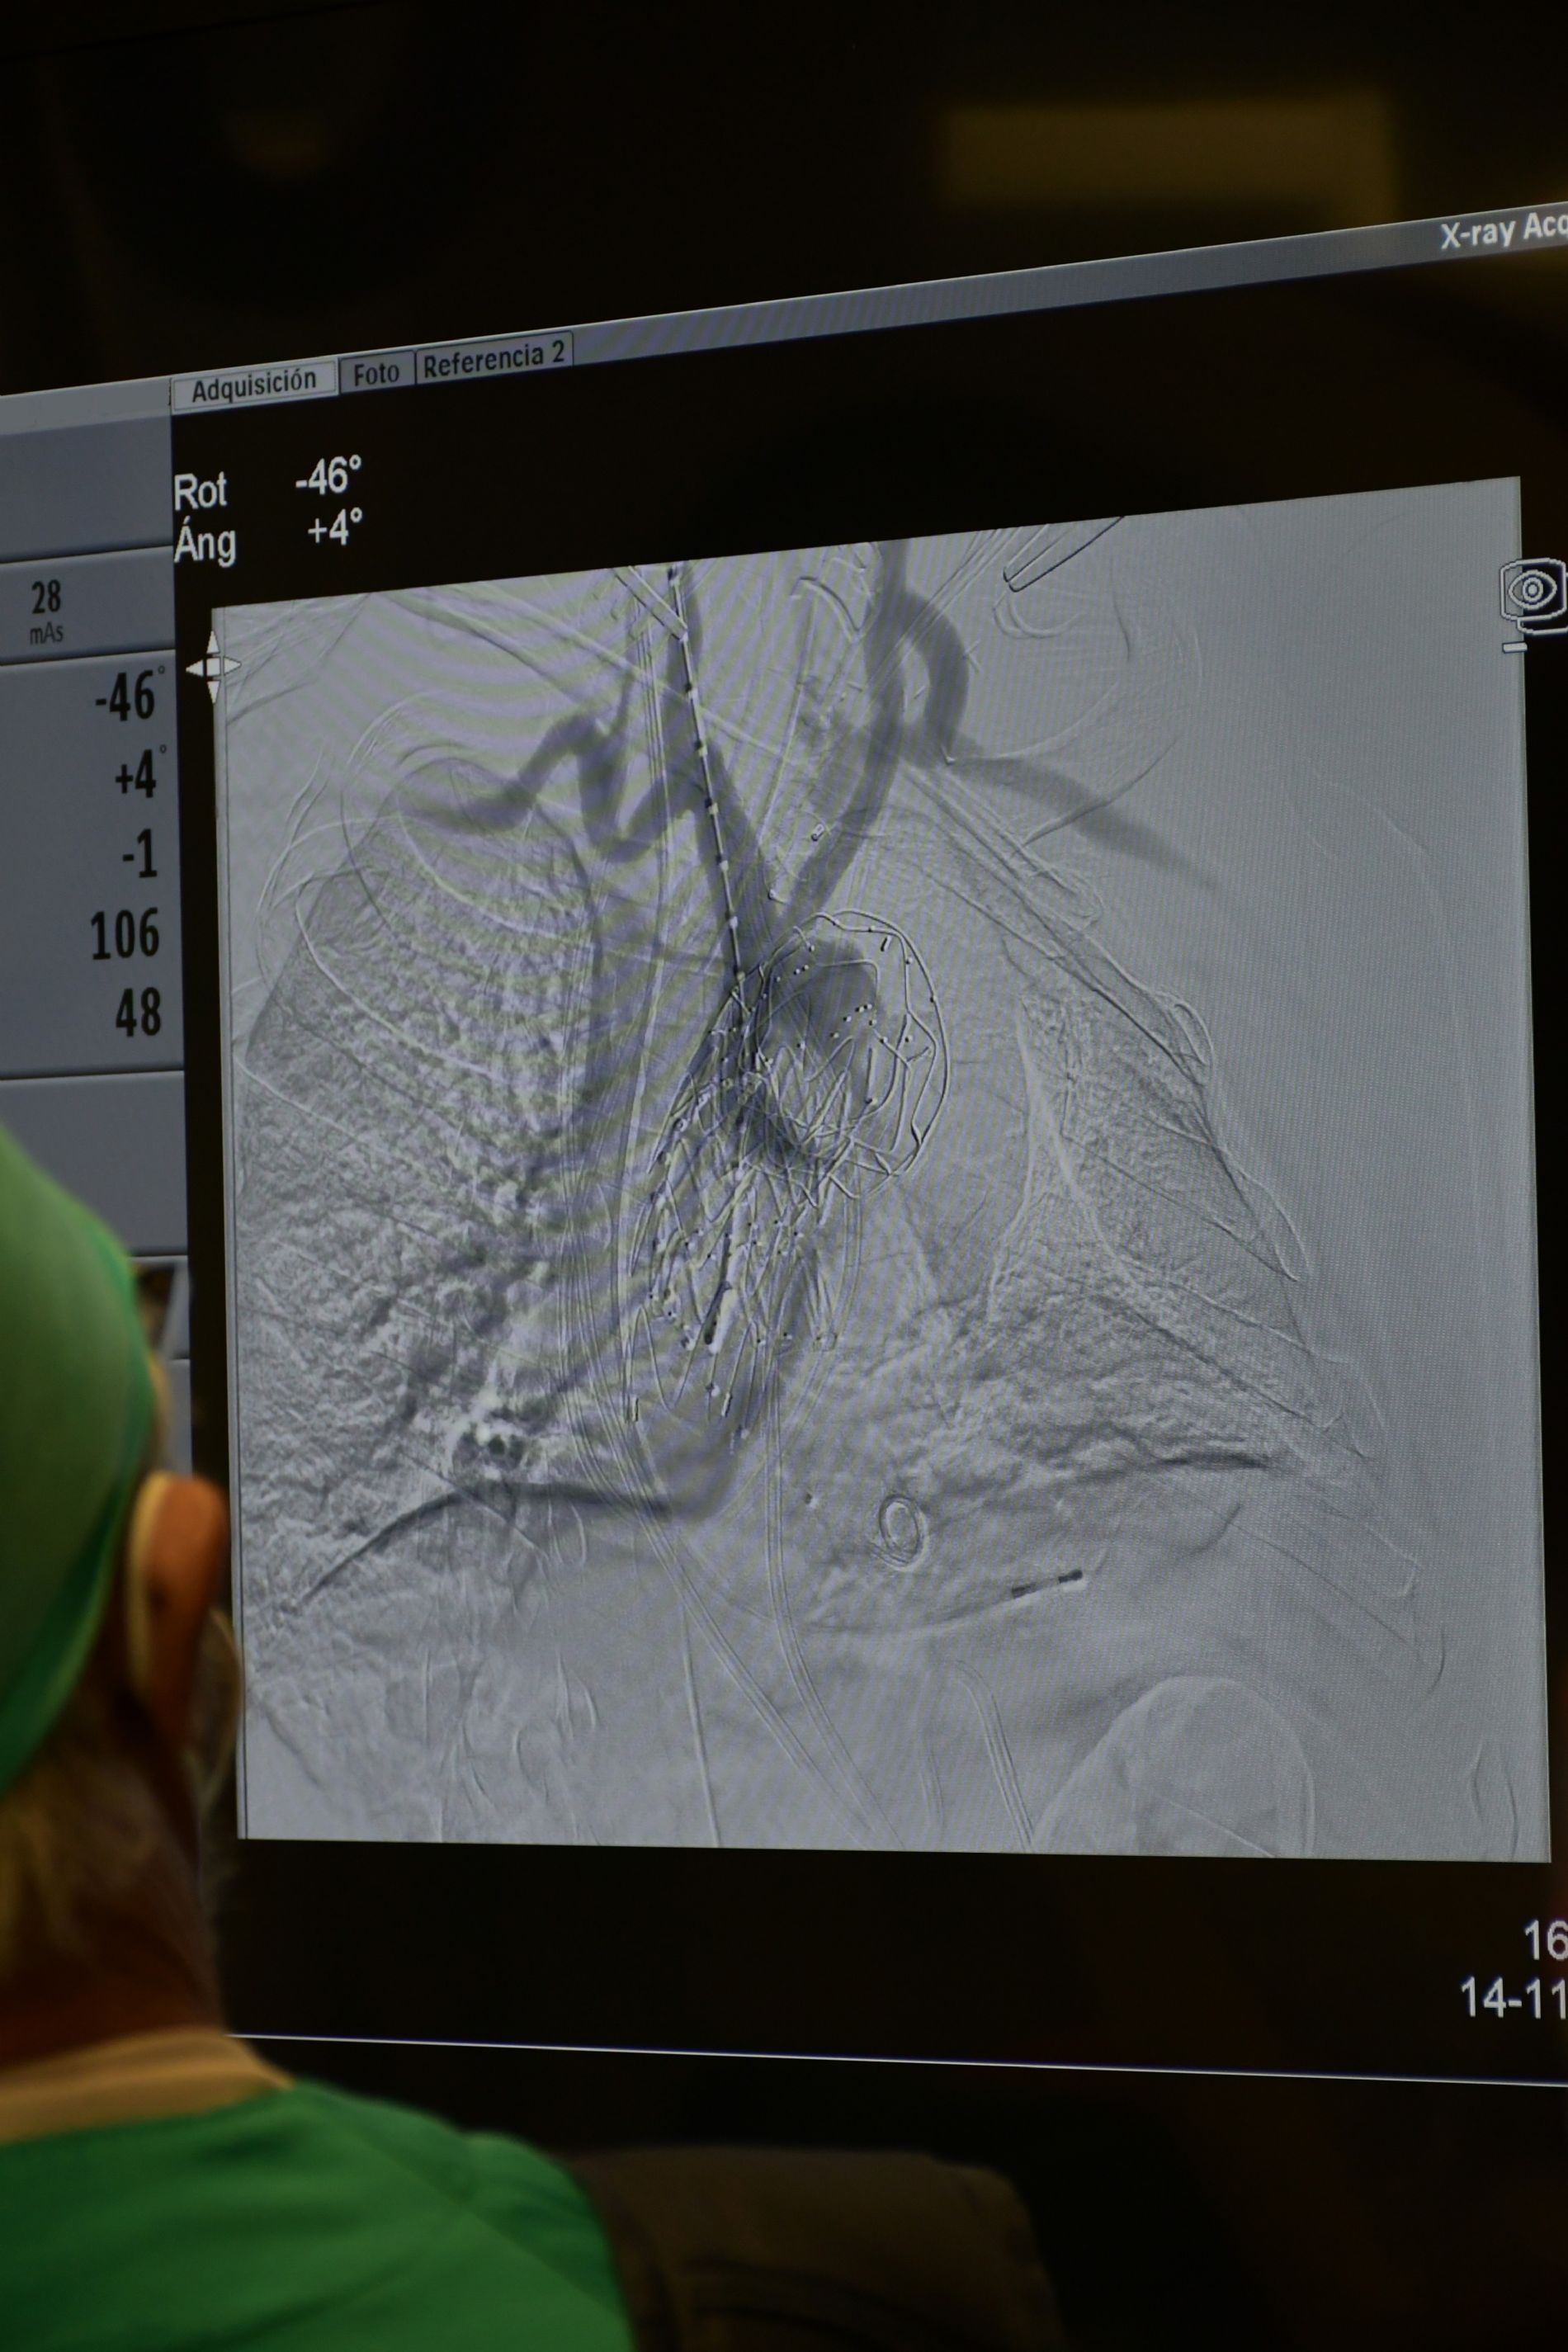

El equipo de Cirugía Vascular del Centro Médico de Asturias, capitaneado por los doctores Hugo Cubillas y Raquel Fernández, junto a su equipo quirúrgico, han implantado por primera vez un dispositivo de doble rama para un aneurisma de aorta. La intervención, que duró un total de siete horas, se llevó a cabo en el quirófano híbrido, dotado de un arco quirúrgico que proporciona en el momento imágenes radiológicas, proporcionando una gran preción a los cirujanos, sin necesitar de trasladar al paciente.

El arco aórtico es el segmento de la aorta torácica que proporciona las ramas de la aorta que dan riego a la cabeza y las extremidades superiores. El aneurisma de arco aórtico es una patología potencialmente grave. Su rotura tiene una mortalidad superior al 97%. "En este paciente se ha realizado el tratamiento de un aneurisma de arco aórtico próximo a los 7 cm de diámetro mediante la colocación de una endoprótesis aórtica de doble rama, a través de una incisión inguinal y 2 incisiones cervicales, evitando así los riesgos asociados a la cirugía tradicional con apertura del tórax", según explica el equipo de Vascular.

El diseño de esta innovadora endoprótesis, "permite mantener la perfusión sanguínea a las carótidas y las extremidades superiores mediante 2 ramas que se conectan a la endoprótesis torácica a nivel del cuello".

Endoprótesis de doble rama